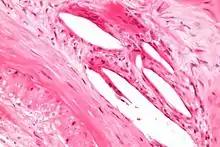

The internal elastic lamina or internal elastic lamella is a layer of elastic tissue that forms the outermost part of the tunica intima of blood vessels. It separates tunica intima from tunica media.

It is readily visualized with light microscopy in sections of muscular arteries, where it is thick and prominent, and arterioles, where it is slightly less prominent and often incomplete.[1] It is very thin in veins and venules.[1] In elastic arteries such as the aorta, which have very regular elastic laminae between layers of smooth muscle cells in their tunica media, the internal elastic lamina is approximately the same thickness as the other elastic laminae that are normally present.[2]

There is small amount of subendothelial connective tissue between basement membrane of endothelial cells and internal elastic lamina.[3]